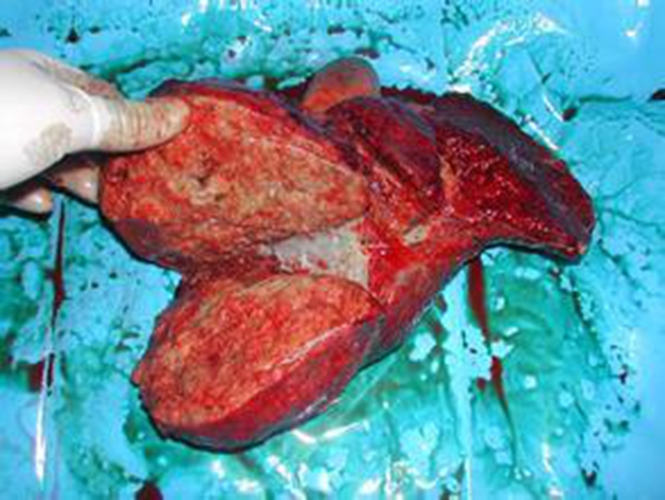

膽管癌圖片

肝門區膽管癌後期症狀

肝門區膽管癌

肝門膽管癌晚期死後

肝門膽管癌晚期